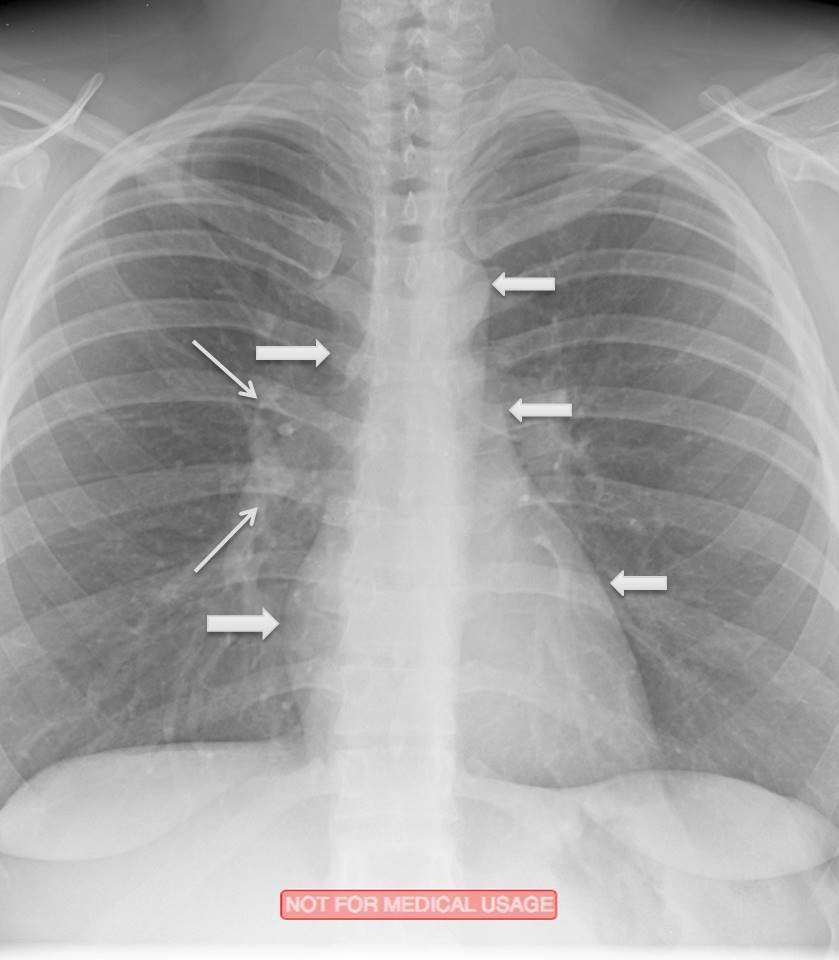

What abnormality do you see here?

What is atelectasis?

•Reduced inflation of all or part of the lung”

•Decreased lung volume with focal increased opacity

(type of consolidation)